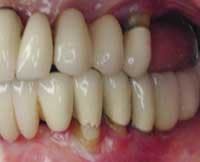

Photos of same woman after implant restoration

The case above is an excellent example in which someone who experiences continued periodontal breakdown around teeth despite treatment will fare better with implants and resist problems with future decay. Dr. Andrew Alpert of Aventura, Fla., placed the implants.

To help a patient understand the benefits of implant restoration, show before and after images of another patient and talk about the stability and improved esthetics achieved.